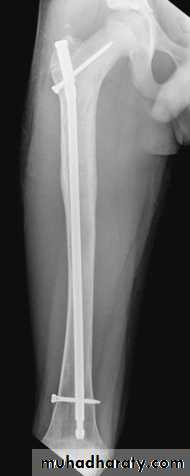

Definitive treatment

closed fractures: by Open reduction and internal fixation, this will decrease the systemic complications..

Fixation of femoral shaft fracture

Exercises for the lower leg and foot are important in preserving muscle tone and in preventing deformity and they should be begin immediately